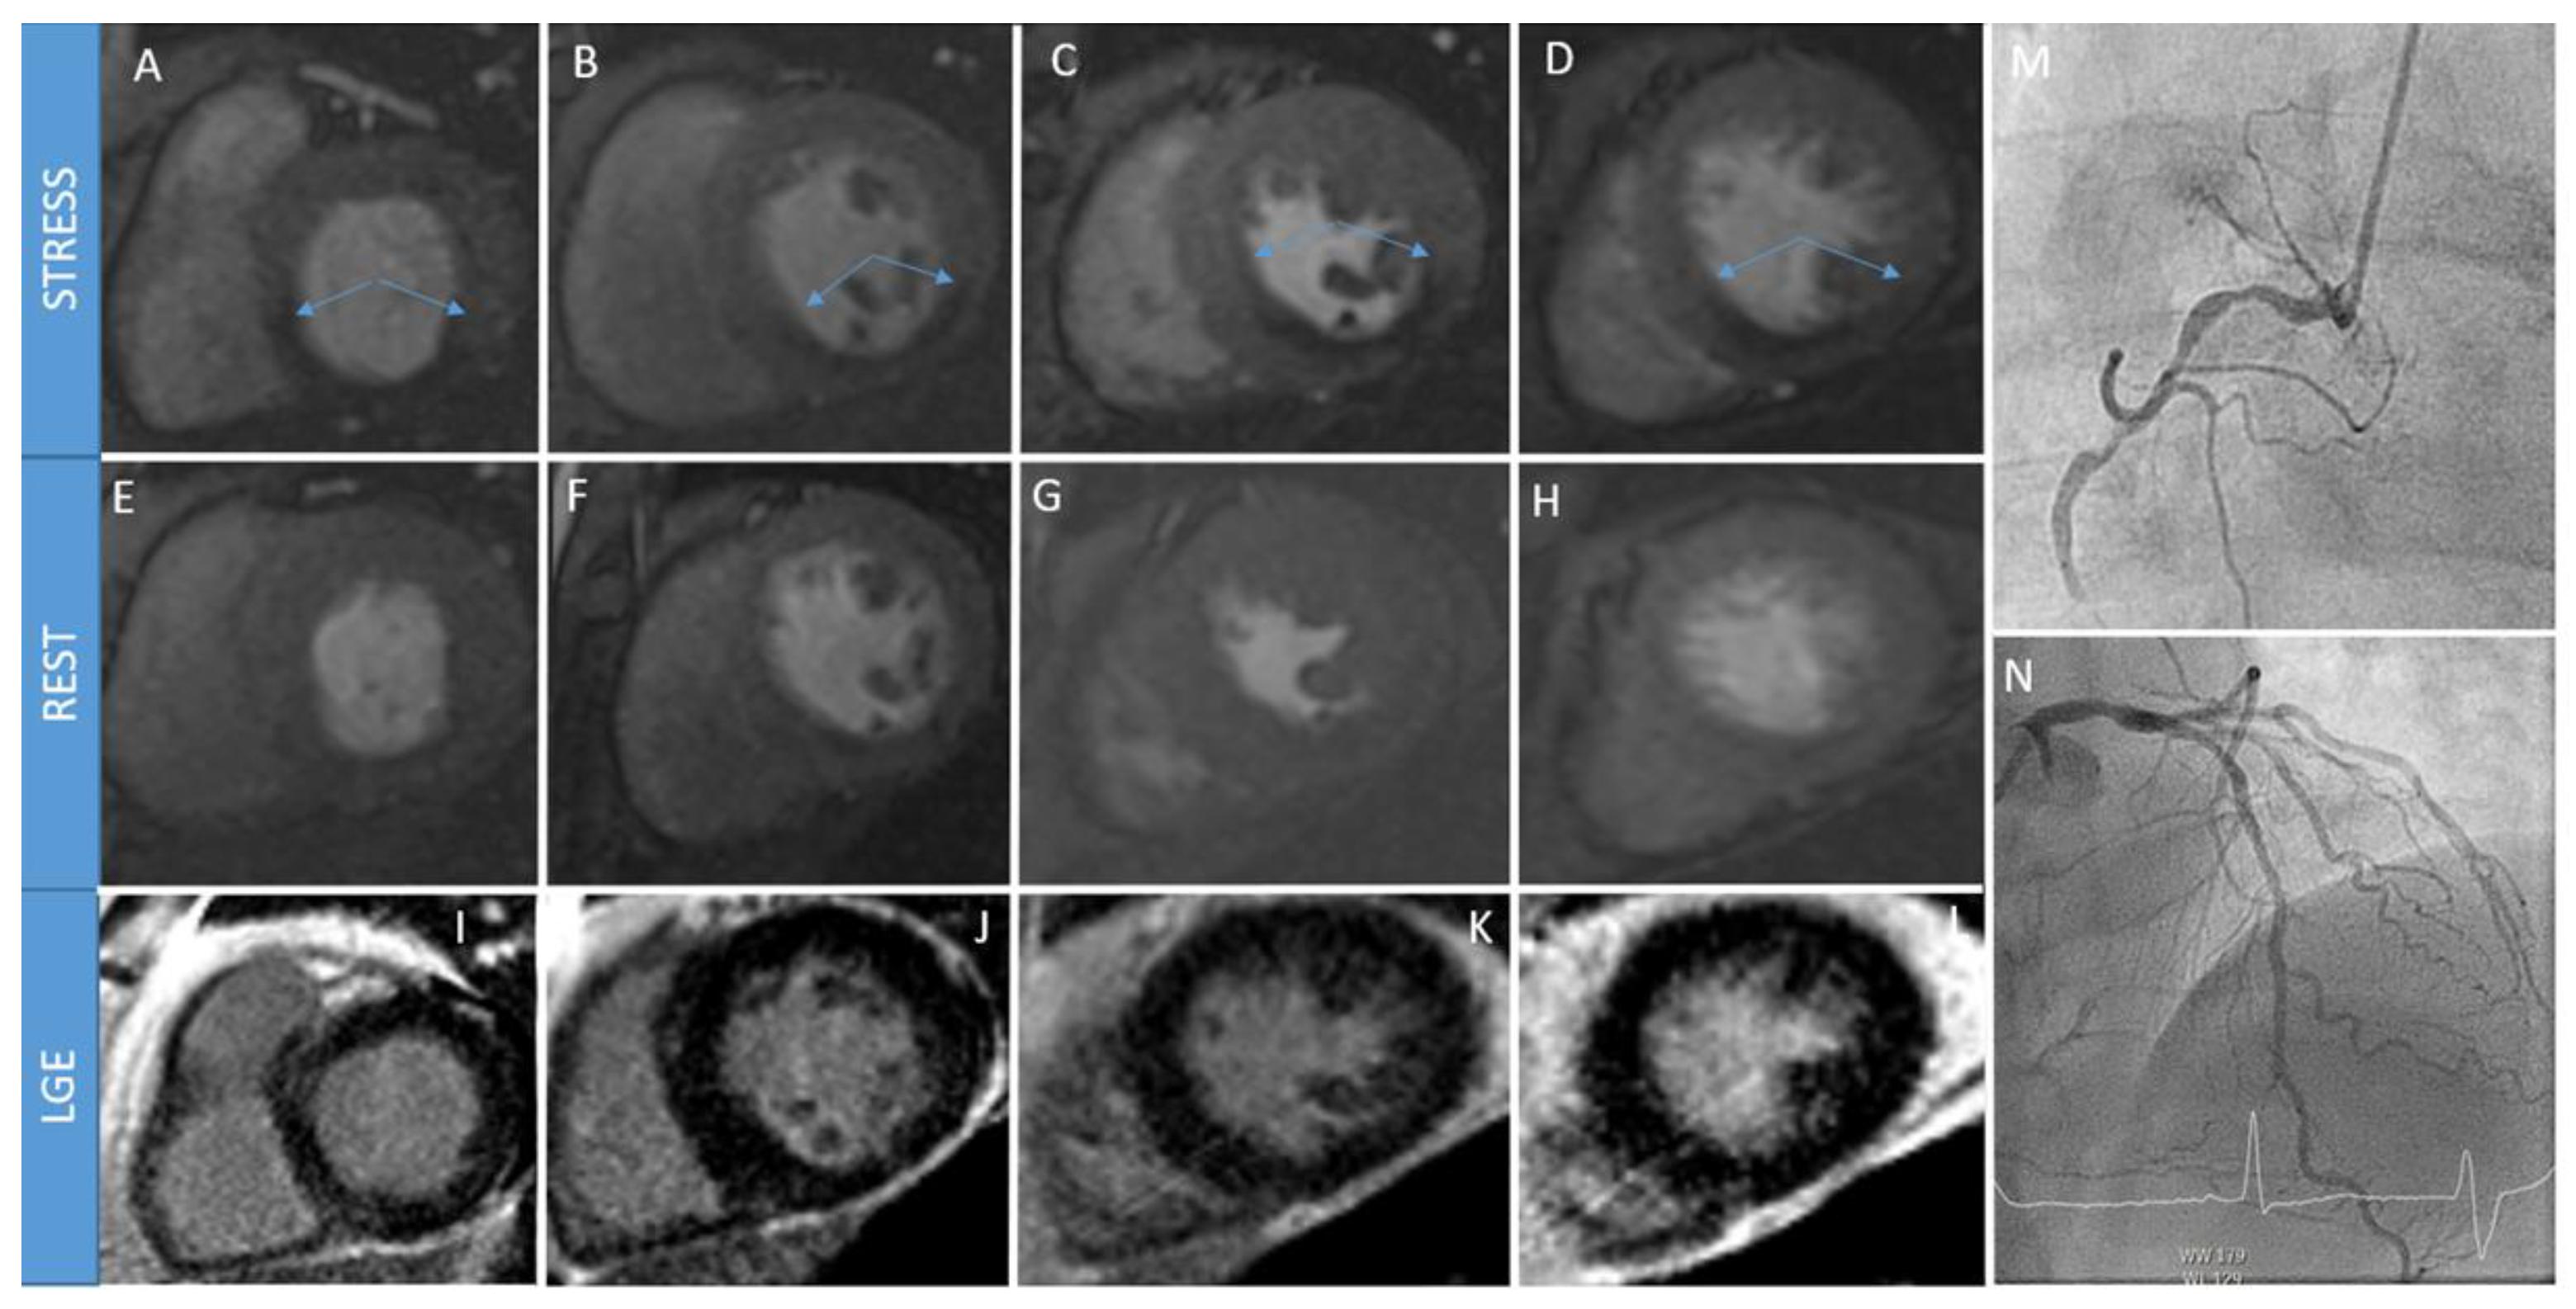

2. Stress Cardiac Magnetic Resonance

2.2. How S-CMR